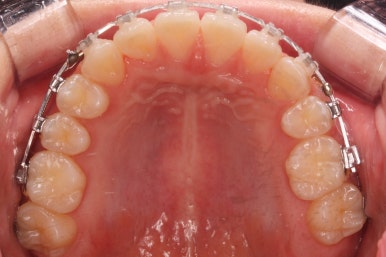

점점 단계가 진행될수록 얼굴의 중앙~윗니의 중앙~아랫니의 중앙이 점점 맞아가고 있음을 알 수 있습니다.

위아래 중앙도 어느 정도 맞아가고 있고, 발치를 한 자리와 결손치아 부위의 틈도 거의 없어져 가고 있습니다.

부산교정 키다리아저씨치과에서는 이번 환자분은 아래 앞니를 3개로 마무리하는 것이 아니라 송곳니를 끌어 당겨와서 앞니처럼 마치 앞니가 4개 있는 것처럼 마무리를 할 계획이어씨 때문에 정면에서 바라보았을 때 앞니 하나가 없는 느낌이 없이 어느 정도 중앙을 맞출 계회이였고, 원할히 진행되고 있음을 알 수 있습니다.